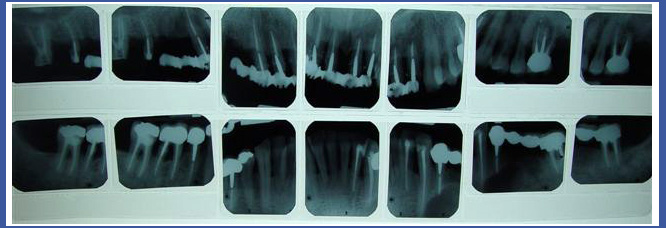

3. Статусный снимок

Это снимок, который выполняется в рентгеновском кабинете и состоит из 14-18 периапикальных снимков, включающих все зубы, которые есть во рту.

Статусный снимок обычно выполняется в качестве диагностической меры в отношении людей, которые проходят/прошли реабилитацию полости рта; людей, у которых существует проблема отслоения костей и десен – снимок позволяет увидеть высоту кости, которая держит зубы.

Часто стоматолог попросит Вас принести статусный снимок, который включает также и снимки прикуса.